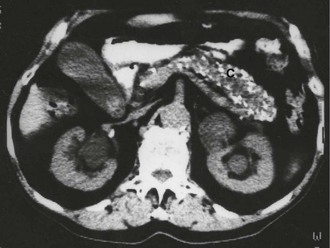

image

Fig. 25.2 Pancreatic pseudocyst

This 57-year-old man was admitted to hospital with an acute abdomen 3 weeks before this scan. He was found to have acute pancreatitis due to gallstones. The symptoms and signs of pancreatitis smouldered on and the CRP and plasma amylase failed to return to normal. This CT scan of his upper abdomen shows the cause of the persistent symptoms, a pseudocyst arising from the tail of the pancreas P